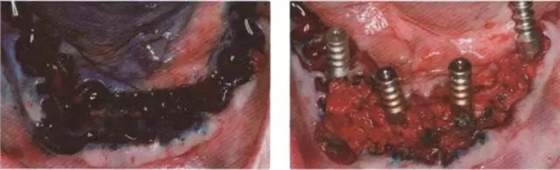

圖3 在46區(qū)種植體的美員側(cè)去骨以清除大部的肉芽組織

圖4 用高濃度的光敏劑(HELB0 bredentmedical公司)作用3分鐘

圖5 用3D_Probe(HELB0 bredenlmedlcal公司)激光激活光敏劑

圖6 術(shù)后影像檢査

圖7 術(shù)后3個月檢查無癥狀,影像檢查發(fā)現(xiàn)在去骨的骨腔內(nèi)開始成骨